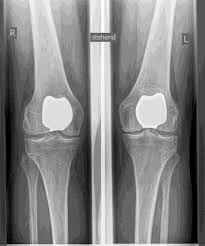

Artificial knee joints are classified as either total or partial replacements. I will carefully determine which prosthesis is suitable for you beforehand, based on a clinical examination, as well as X-rays or MRI scans.

The artificial knee joint replaces the cartilage surface destroyed by osteoarthritis. The underlying bone of the femur and tibia remains intact. Some compare a modern artificial knee joint to a

crown on a tooth; the precise term is

bicondylar resurfacing. Between the new surfaces of the femur and tibia is an inlay made of a specially hardened white plastic, visible in X-rays as a gap between the metal components.